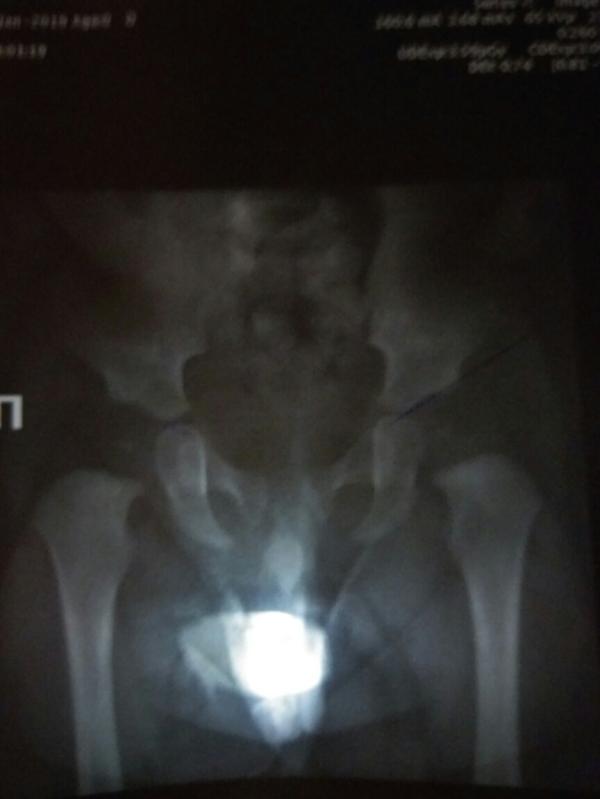

В общем. Переделали мы рентген. По его результатам один угол у нас все равно больше нормы, он 28град. Ортопед намерил 30. Ядра появились и они симметричны.

Никакой фиксации не требуется, если сын сам встает, пусть встаёт. Вот вердикт ортопеда. Он вовсе написал Здоров. Да, один угол по нормам трехмесячного ребёнка, но для него просто нужен рентген контроль, лфк, массаж и физио для улучшения кровообращения. Все.

Сам рентген в карусели, если кто разбира...